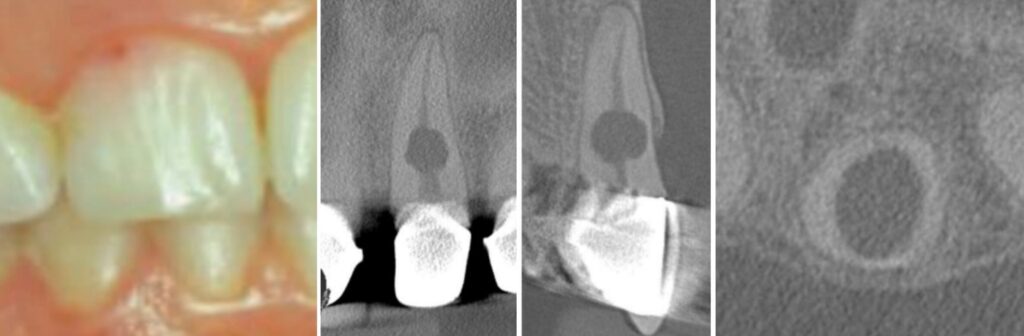

You got internal resorption—starts from the pulp, eats out the inside of the root like a termite in your floorboards. Pink spot on the crown? That ain’t cosmetics, that’s a warning light, brother

Internal resorption